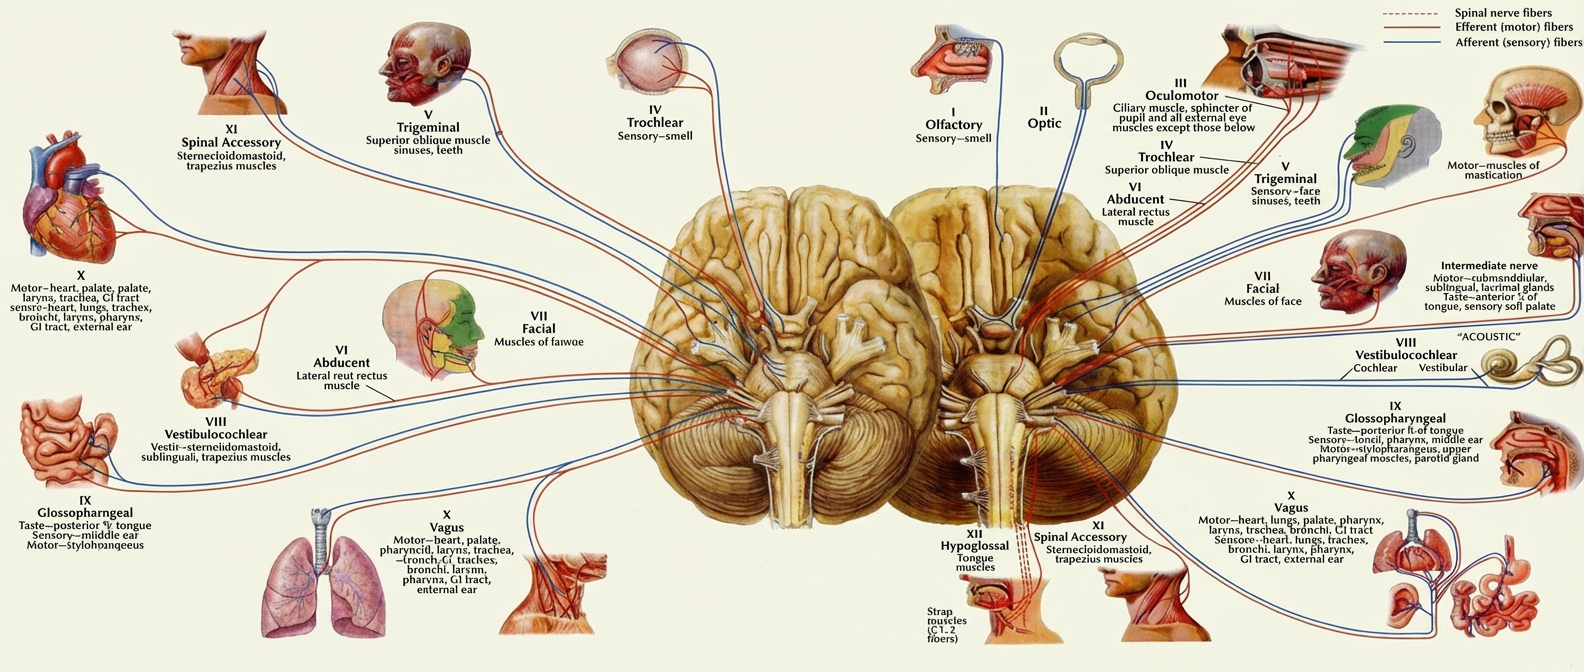

Read MoreNeurology

Neurology is the medical specialty that focuses on the diagnosis and treatment …